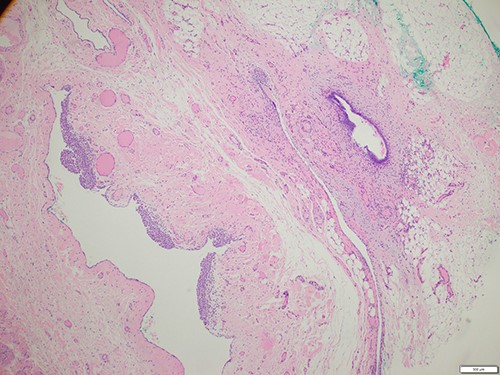

The patient was referred for an ultrasound (US) of the left groin, which showed a contained cyst in the inguinal canal consistent with a CCN (Fig. 1). She was referred to a general surgeon for elective surgical management. A herniorrhaphy was performed with excision of the canal of Nuck and mesh repair. The procedure occurred without complication and the patient was discharged the following day. Histopathology report confirmed a CCN as well as evidence of endometriosis in the adjacent tissue (Fig. 2).

Histology of the surgical specimen (×40 magnification) shows a cystic structure lined in part by cuboidal epithelium in keeping with a cyst of canal of Nuck; focal endometriosis is identified in the adjacent soft tissue.

Clinically, CCN presents as a palpable, fluctuant, reducible or irreducible swelling in the inguinolabial region, which can be either painless or moderately painful [6]. Omental and intestinal contents may also herniate through a patent canal of Nuck, and approximately one-third of patients with a CCN can have a concurrent inguinal hernia requiring simultaneous repair [5]. Additionally, a patent canal of Nuck is a rare but potential location for seeding of endometrial tissue, with a prevalence of 0.3–0.6% of all endometriosis cases [7]. Theories for extra-pelvic endometriosis include retrograde menstruation, hematogenous or lymphatic spread or coelomic metaplasia [7, 8]. A female groin mass implicated with endometriosis is more likely to present with cyclical pain consistent with menstruation.